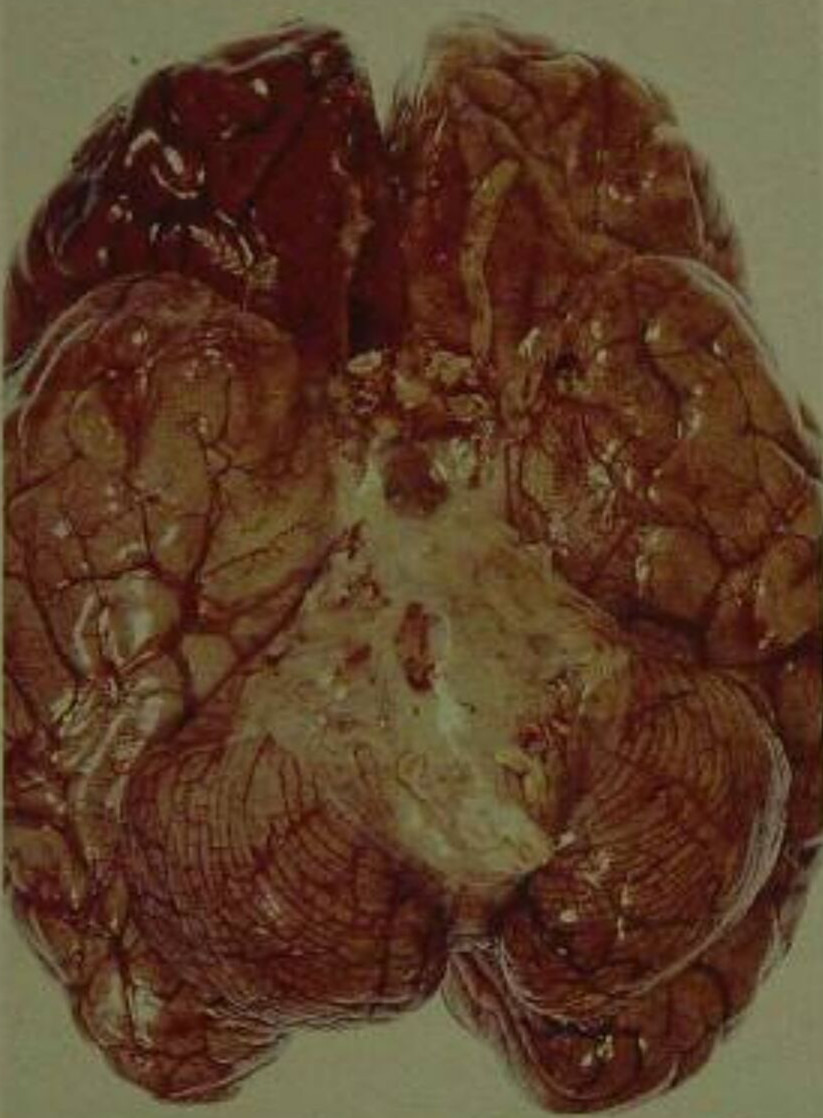

腦膜炎末期

腦膜炎細菌性的腦部的